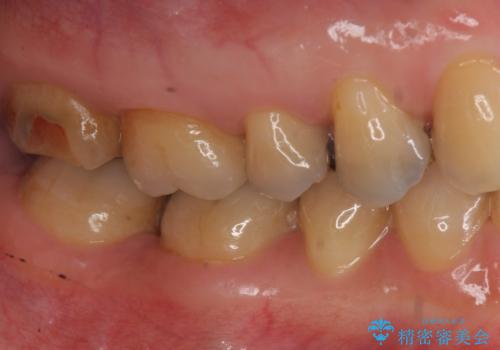

- 右下奥歯の詰め物が取れたとのことで来院されました。

セラミックでの治療をご希望されましたが、残っている歯が少なかったためクラウンでの治療を行いました。

もう一つ奥の歯に関してもセラミックにやり替えたいとのことでしたので、こちらはインレーでの治療を行いました。

残る歯が薄かったり、十分な量を確保できない場合はクラウンで治療した方が今後の破折リスクを抑えることができます。